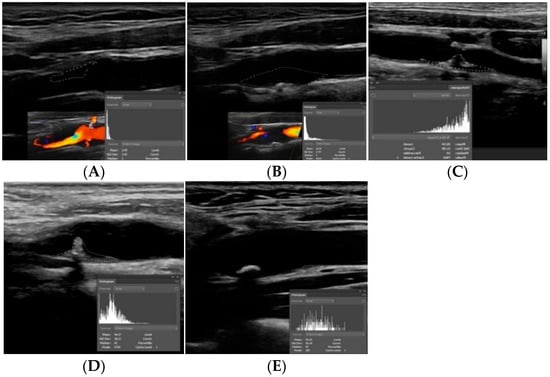

- Huang, Z.; Cheng, X.Q.; Liu, H.Y.; Bi, X.J.; Liu, Y.N.; Lv, W.Z.; Xiong, L.; Deng, Y.B. Relation of Carotid Plaque Features Detected with Ultrasonography-Based Radiomics to Clinical Symptoms. Transl. Stroke Res. 2021. [Google Scholar] [CrossRef] [PubMed]

- Rafailidis, V.; Chryssogonidis, I.; Grisan, E.; Xerras, C.; Cheimariotis, G.A.; Tegos, T.; Rafailidis, D.; Sidhu, P.S.; Charitanti-Kouridou, A. Does Quantification of Carotid Plaque Surface Irregularities Better Detect Symptomatic Plaques Compared to the Subjective Classification? J. Ultrasound Med. Off. J. Am. Inst. Ultrasound Med. 2019, 38, 3163–3171. [Google Scholar] [CrossRef]

- Kanber, B.; Hartshorne, T.C.; Horsfield, M.A.; Naylor, A.R.; Robinson, T.G.; Ramnarine, K.V. A Novel Ultrasound-Based Carotid Plaque Risk Index Associated with the Presence of Cerebrovascular Symptoms. Ultraschall Med. 2015, 36, 480–486. [Google Scholar] [CrossRef] [PubMed]

- Rafailidis, V.; Chryssogonidis, I.; Xerras, C.; Grisan, E.; Cheimariotis, G.A.; Tegos, T.; Rafailidis, D.; Sidhu, P.S.; Charitanti-Kouridou, A. An Ultrasonographic Multiparametric Carotid Plaque Risk Index Associated with Cerebrovascular Symptomatology: A Study Comparing Color Doppler Imaging and Contrast-Enhanced Ultrasonography. Am. J. Neuroradiol. 2019, 40, 1022–1028. [Google Scholar] [CrossRef] [PubMed]

- Kanber, B.; Hartshorne, T.C.; Horsfield, M.A.; Naylor, A.R.; Robinson, T.G.; Ramnarine, K.V. Quantitative assessment of carotid plaque surface irregularities and correlation to cerebrovascular symptoms. Cardiovasc. Ultrasound 2013, 11, 38. [Google Scholar] [CrossRef] [PubMed]